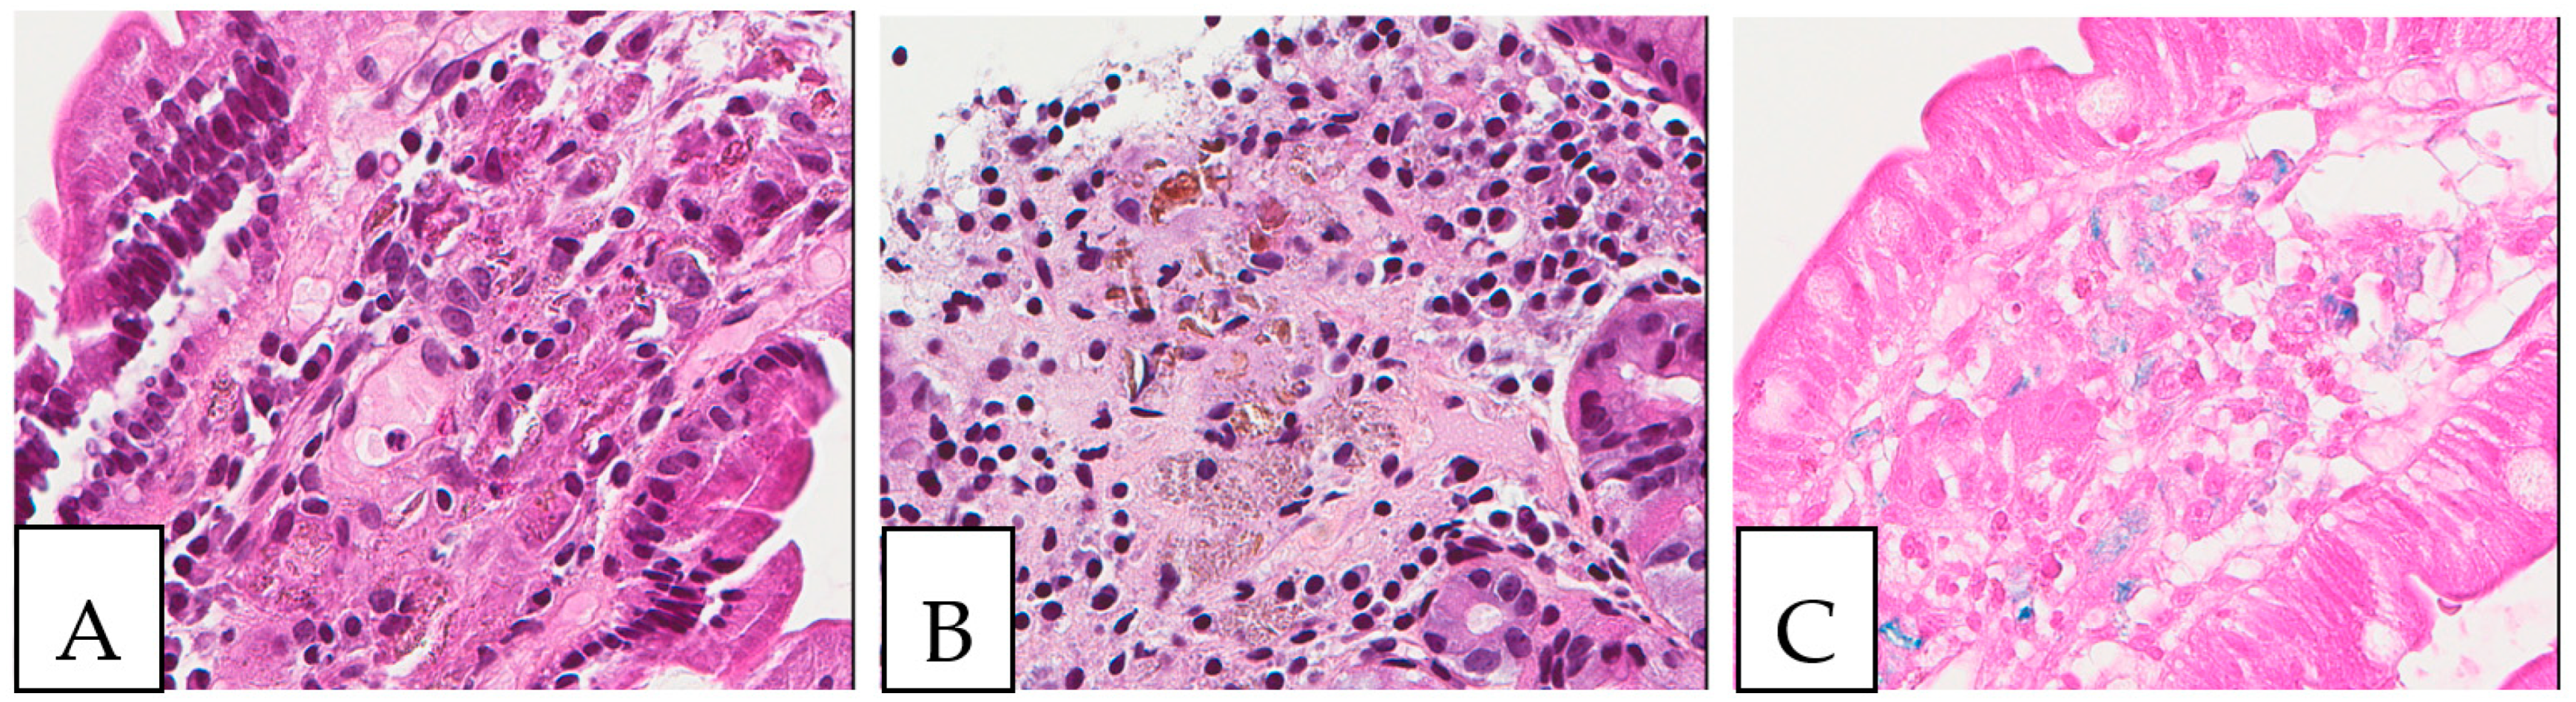

5. Pathologic Features